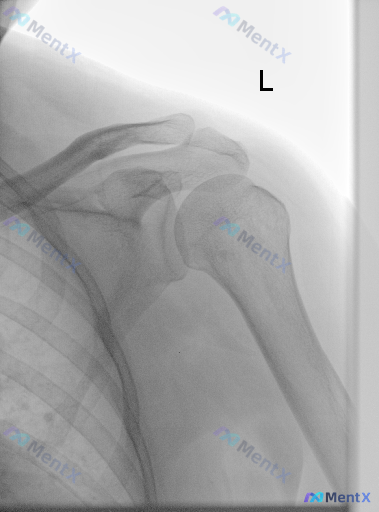

整理了一份左侧肩关节正位片的影像资料,报告结论很明确:未见明显骨性异常、急性外伤或严重退变。 但有意思的地方就在这里:如果拿到这份报告的患者,刚好有明显的肩痛、夜间痛、甚至外展无力,你第一眼会怎么考虑? 先放核心读片结果: - 骨骼:肱骨头、肩胛骨、锁骨远端完整,无骨折/脱位/骨质破坏 - 关节:盂...

整理了一份左侧肩部正位X光片的临床分析资料,有点意思: 影像上明确说了: - 肱骨头、肩胛盂、锁骨这些骨性结构都完整,没骨折、没脱位、没骨质破坏 - 关节间隙好,没有明显骨赘、囊性变 - 肩袖附着区没看到钙化 - 软组织也没明显肿胀、积气 - 一句话:未见明确骨性异常 但问题来了:如果这个患者是因为...